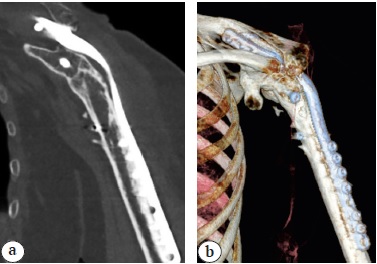

At the time of article writing, 100 patients underwent surgery according to the above-mentioned indications in the clinic of the R.R. Vreden NMIC TO according to the described technique. Over the past 5 years, the ratio of revision indications together with the contraindications to arthroplasty to all other indications has increased to 3:2. In 95% of patients, ankylosis of the shoulder joint was formed, and consolidation in the absence of the head and defects of the glenoid led to the formation of a sufficiently strong bone callus (Fig. 4). In some patients without final callus remodeling, clinical consolidation is observed with a positive tendency to bone fusion. All patients note the pain relief, physical strength increasing and consistency of the result with a tendency to improve by the 5th-6th year after surgery without a tendency to deterioration for 10 years.

Fig. 4. Consolidation quality after left shoulder fusion for recurrent dislocations after the revision reverse arthroplasty (7 years of anatomical endoprosthesis survival, & 4 years after the reverse shoulder arthroplasty complicated by recurrent dislocations): а — CT-scan frontal section; b — CT-scan, 3D reconstruction, frontal view